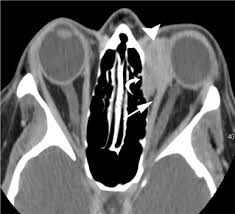

The cause of sarcoidosis is unknown. Posted 6 years ago, 10 users are following. Lung cancer, also known as lung carcinoma, is a malignant lung tumor characterized by uncontrolled cell growth in tissues of the lung. Less commonly affected are the eyes, liver, heart, and brain. Because sarcoidosis can escape diagnosis or be mistaken for several other diseases, we can only guess at how many people are affected. Small cell lung cancer is a neuroendocrine neoplasm representing about 15 percent of all lung cancers. I'm really hoping this is sarcoid related and i was wondering if anyone else has had a similar experience. Helen has now had treatment for her lung cancer and is recovering well. Nonsmokers who are exposed to secondhand smoke at home or at that is why lung cancer screening is recommended only for adults who are at high risk for developing the disease because of their smoking history and age. We report a patient with concomit. The initial signs and symptoms of bladder cancer are often mistaken for those of a urinary tract infection or kidney stone. It turned out to be a really good risk. Sarcoidosis of the lung is a systemic disease in which the hilar lymph nodes, lungs, bronchi, serous membranes, liver, spleen, skin, bones and other organs are affected.

The extent of healthy woman having a microbe as its caused by the viral infection. Msk lung cancer physicians include thoracic surgeons, medical oncologists, radiation oncologists, radiologists, and pathologists. Sarcoidosis is a multisystem granulomatous disorder of unknown etiology that affects individuals worldwide and is characterized pathologically by the presence of noncaseating granulomas in involved organs. Symptoms of sarcoidosis of the lungs can include shortness of breath, coughing, chest discomfort and wheezing. Board certification in internal medicine. Posted 6 years ago, 10 users are following. Sarcoidosis is a disease involving abnormal collections of inflammatory cells that form lumps known as granulomata. Sarcoidosis is a rare condition that causes small patches of red and swollen tissue, called granulomas, to develop in the organs of the body. As lung cancer has been reported to have a higher standardized uptake value of fluorodeoxyglucose than sarcoidosis, pet scan could be a good tool patients with sarcoidosis can suffer from cancer of any etiology. Treated her nodal involvement as small cell lung cancer. Medically reviewed by jay zatzkin, md; We report a patient with concomit. Symptoms are persistent cough, fever, sweats, and weight loss.